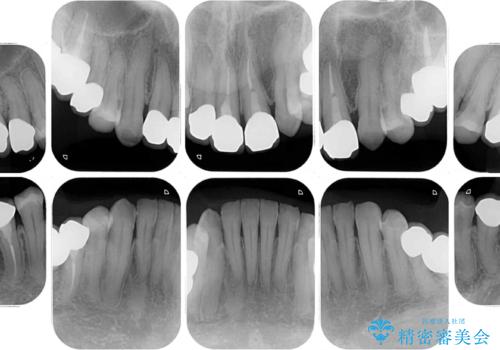

- 全顎的な歯列不正と、銀歯だらけの奥歯を気にして来院された患者様です。

奥歯の銀歯は、セラミッククラウンを装着するには歯の高さが不十分であり、そのままでは矯正治療を行うことが困難であるため、歯冠長延長術を行うこととしました。

また、根管治療の必要な歯がいくつかあるため、歯周外科治療の治癒期間を利用して根管治療を行い、その後インビザラインにて矯正治療を行うこととしました。